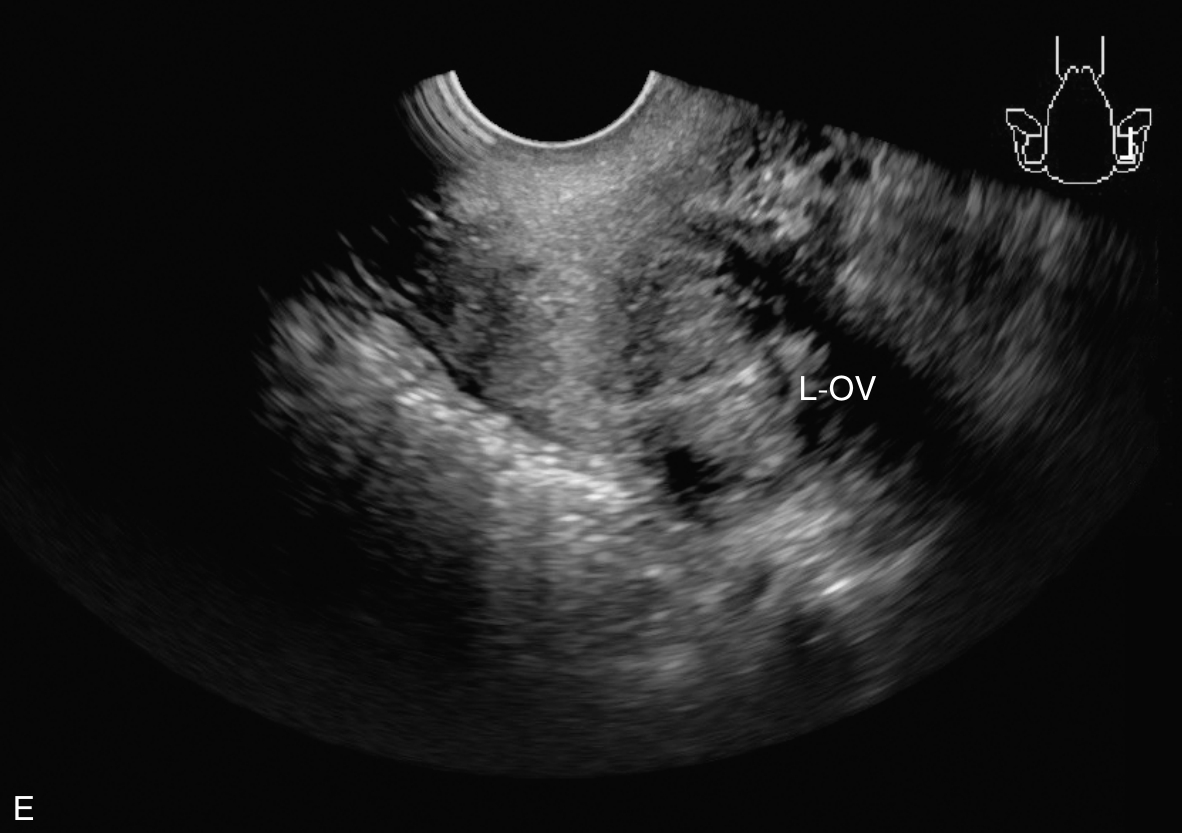

经阴道超声检查见图3-5-1。子宫后位,宫体大小约5.8cm×5.0cm×5.1cm,宫内膜厚约0.75cm(单层),内膜回声不均匀。宫腔未见分离。宫壁回声均匀。内膜内见多个囊性结节,较大者大小约0.5cm,内透声可。CDFI:未见异常血流信号。双侧附件区未见异常回声。盆腹腔未见明显积液。超声检查结果:宫内膜增厚伴回声不均匀。

图3-5-1 常规超声声像图

A.后位子宫的矢状切面(经阴道),子宫内膜增厚,单层厚约0.75cm,内见多个小暗区;B.后位子宫的横断面(经阴道);C.后位子宫的矢状切面(经阴道),彩色多普勒能量图超声检查显示子宫未探及明显血流信号;D.右卵巢;E.左卵巢。UT:子宫;EN:子宫内膜;R-OV:右卵巢;L-OV:左卵巢。